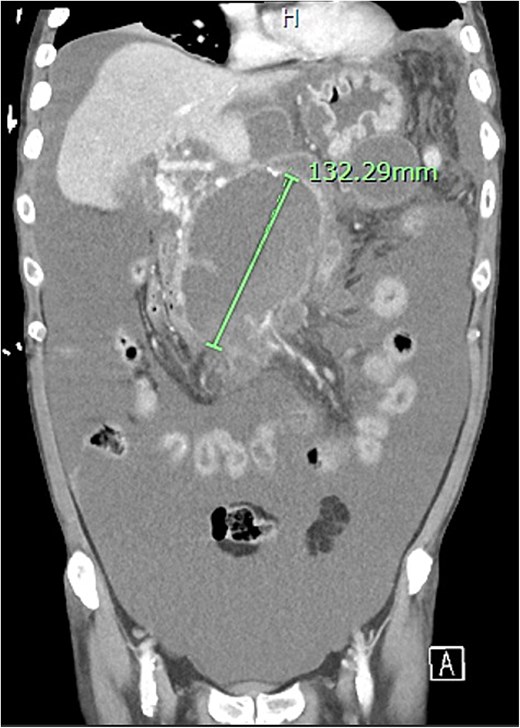

Despite the absence of abdominal symptoms, a computed tomography of the abdomen and pelvis (CTAP) was performed due to markedly elevated lipase levels. The CTAP (Figs 3–5) revealed evidence of acute pancreatitis (Fig. 5, arrow), with a complex peripancreatic fluid collection (Fig. 3, arrow). Additionally, a focal thrombus was observed within the portal venous confluence (Fig. 4, arrow). Further ultrasound of the gallbladder was negative for gallstones (Fig. 6), ruling out gallstone-induced pancreatitis.

CTAP coronal view; complex peripancreatic fluid collection (arrow) with extension behind the splenic vein to lie adjacent to the pancreatic neck and uncinate process.